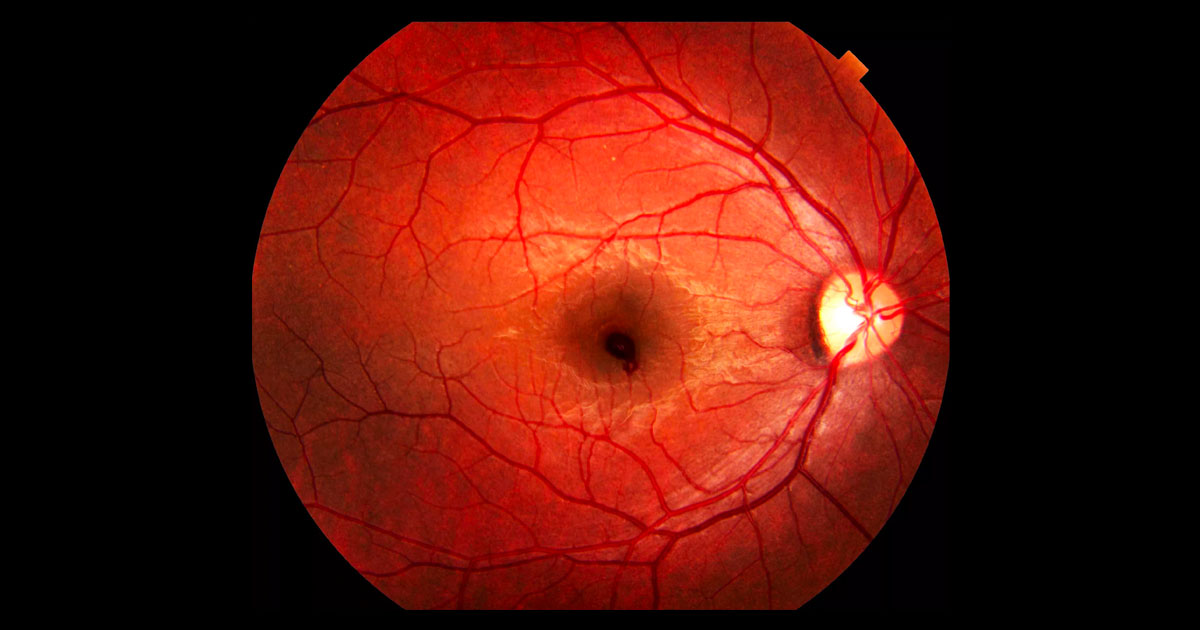

Изображения и анатомия сетчатки глаза

Раздел: Визуальный дайджест